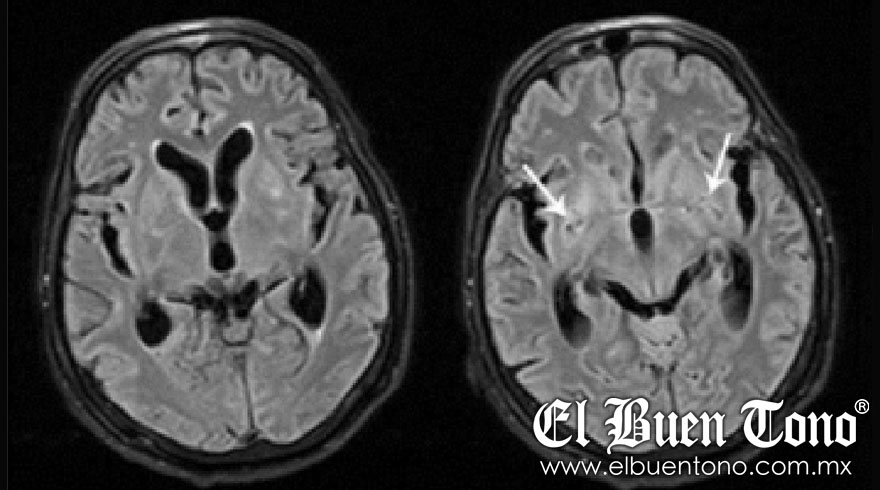

La Secretaría de Salud de Durango informó por medio de una actualización que la entidad cuenta con 68 casos confirmados y 21 fallecimientos por meningitis derivada de un hongo que ha ocasionado un brote de la enfermedad en la entidad a lo largo de las últimas semanas.

El pasado 1 de diciembre, el Subsecretario Hugo López-Gatell explicó que se trata de un brote que se detectó en cuatro hospitales privados de la entidad norteña, mismos que ya fueron clausurados como medida de precaución.

“La presunta causa de infección entre los pacientes fue a través de un procedimiento de anestesia. Hay un tipo de anestesia que se pone por medio de agujas directamente a la médula espinal y este tipo de procedimientos se utilizan en todo el país y en todo el mundo pues es un procedimiento estandarizado que, en condiciones habituales, es completamente seguro”, refirió el funcionario.